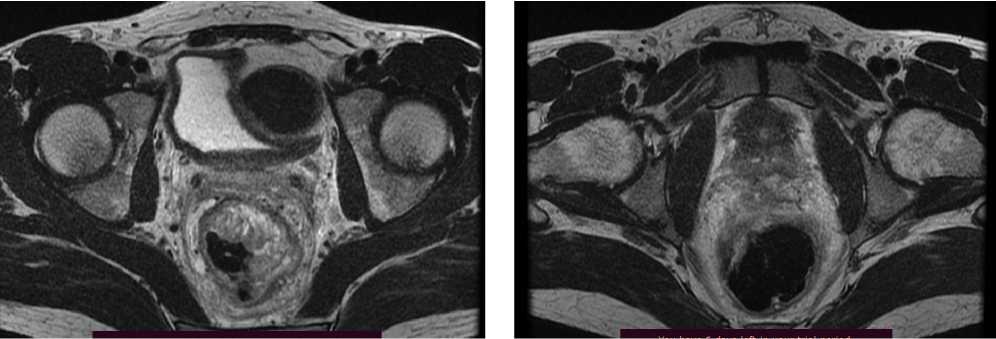

По решению онкологического консилиума пациенту начат ПХТ 1 линии в режиме FOLFOX + бевацизумаб. С 02.09.2022 проведено 3 цикла ПХТ 1 линии, по результатам контрольных обследований зарегистрировано прогрессирование процесса за счет роста образований печени до 64 × 46 мм и появления линзовидного образования между передней поверхностью прямой кишки и задней поверхностью предстательной железы размерами 47 × 15 × 25 мм (рис. 7, 8).

Рис. 7. Результаты компьютерной томографии органов брюшной полости у пациента 37 лет с диагнозом метастатический колоректальный рак с признаками микросателлитной нестабильности (октябрь 2022 г., после 3-х циклов FOLFOX + бевацизумаб)

Fig. 7. Results of abdominal CT scan in a 37-year-old patient diagnosed with metastatic MSI-H colorectal cancer (October 2022, after 3 cycles of FOLFOX + bevacizumab)

Рис. 8. Результаты магнитно-резонансной томографии органов брюшной полости у пациента 37 лет с диагнозом метастатический колоректальный рак с признаками микросателлитной нестабильности (октябрь 2022 г., после 3-х циклов FOLFOX + бевацизумаб)

Fig. 8. Results of abdominal MRI in a 37-year-old patient diagnosed with metastatic MSI-H colorectal cancer (October 2022, after 3 cycles of FOLFOX + bevacizumab)

В октябре 2022 г. получены результаты иммуногистохимического исследования на предмет MSI, выявлена утрата ядерной экспрессии MLH1 и PMS2.

С учетом результатов ИГХ, прогрессирования процесса по результатам контрольных обследований, пациенту начата 2 линия системного лечения пембролизумабом в монорежиме.

С ноября 2022 г. выполнено 14 введений пембролизумаба с максимальным эффектом частичный регресс (образование между передней поверхностью прямой кишки и задней поверхностью предстательной железы регрессировало полностью). По результатам контрольных обследований (КТ ОБП и МРТ ОМТ от сентября 2023 г.) сохраняются очаги в печени до 21 × 11 мм, а также опухоль средне- и верхнеампулярного отделов прямой кишки с выраженным муцинозным компонентом. МР-стадия Т4а (CRM+, EMVI+) (рис. 9, 10).

Рис. 10. Частичный регресс, по данным магнитно-резонансной томографии органов брюшной полости, на фоне иммунотерапии пембролизумабом у пациента 38 лет с диагнозом метастатический колоректальный рак с признаками микросателлитной нестабильности; МР-стадия Т4а (CRM+, EMVI+) (сентябрь 2023 г.)

Fig. 10. Partial response according to abdominal magnetic resonance imaging during immunotherapy with pembrolizumab in a 38-year-old patient diagnosed with metastatic MSI-H colorectal cancer; MR stage T4a (CRM+, EMVI+) (September 2023)